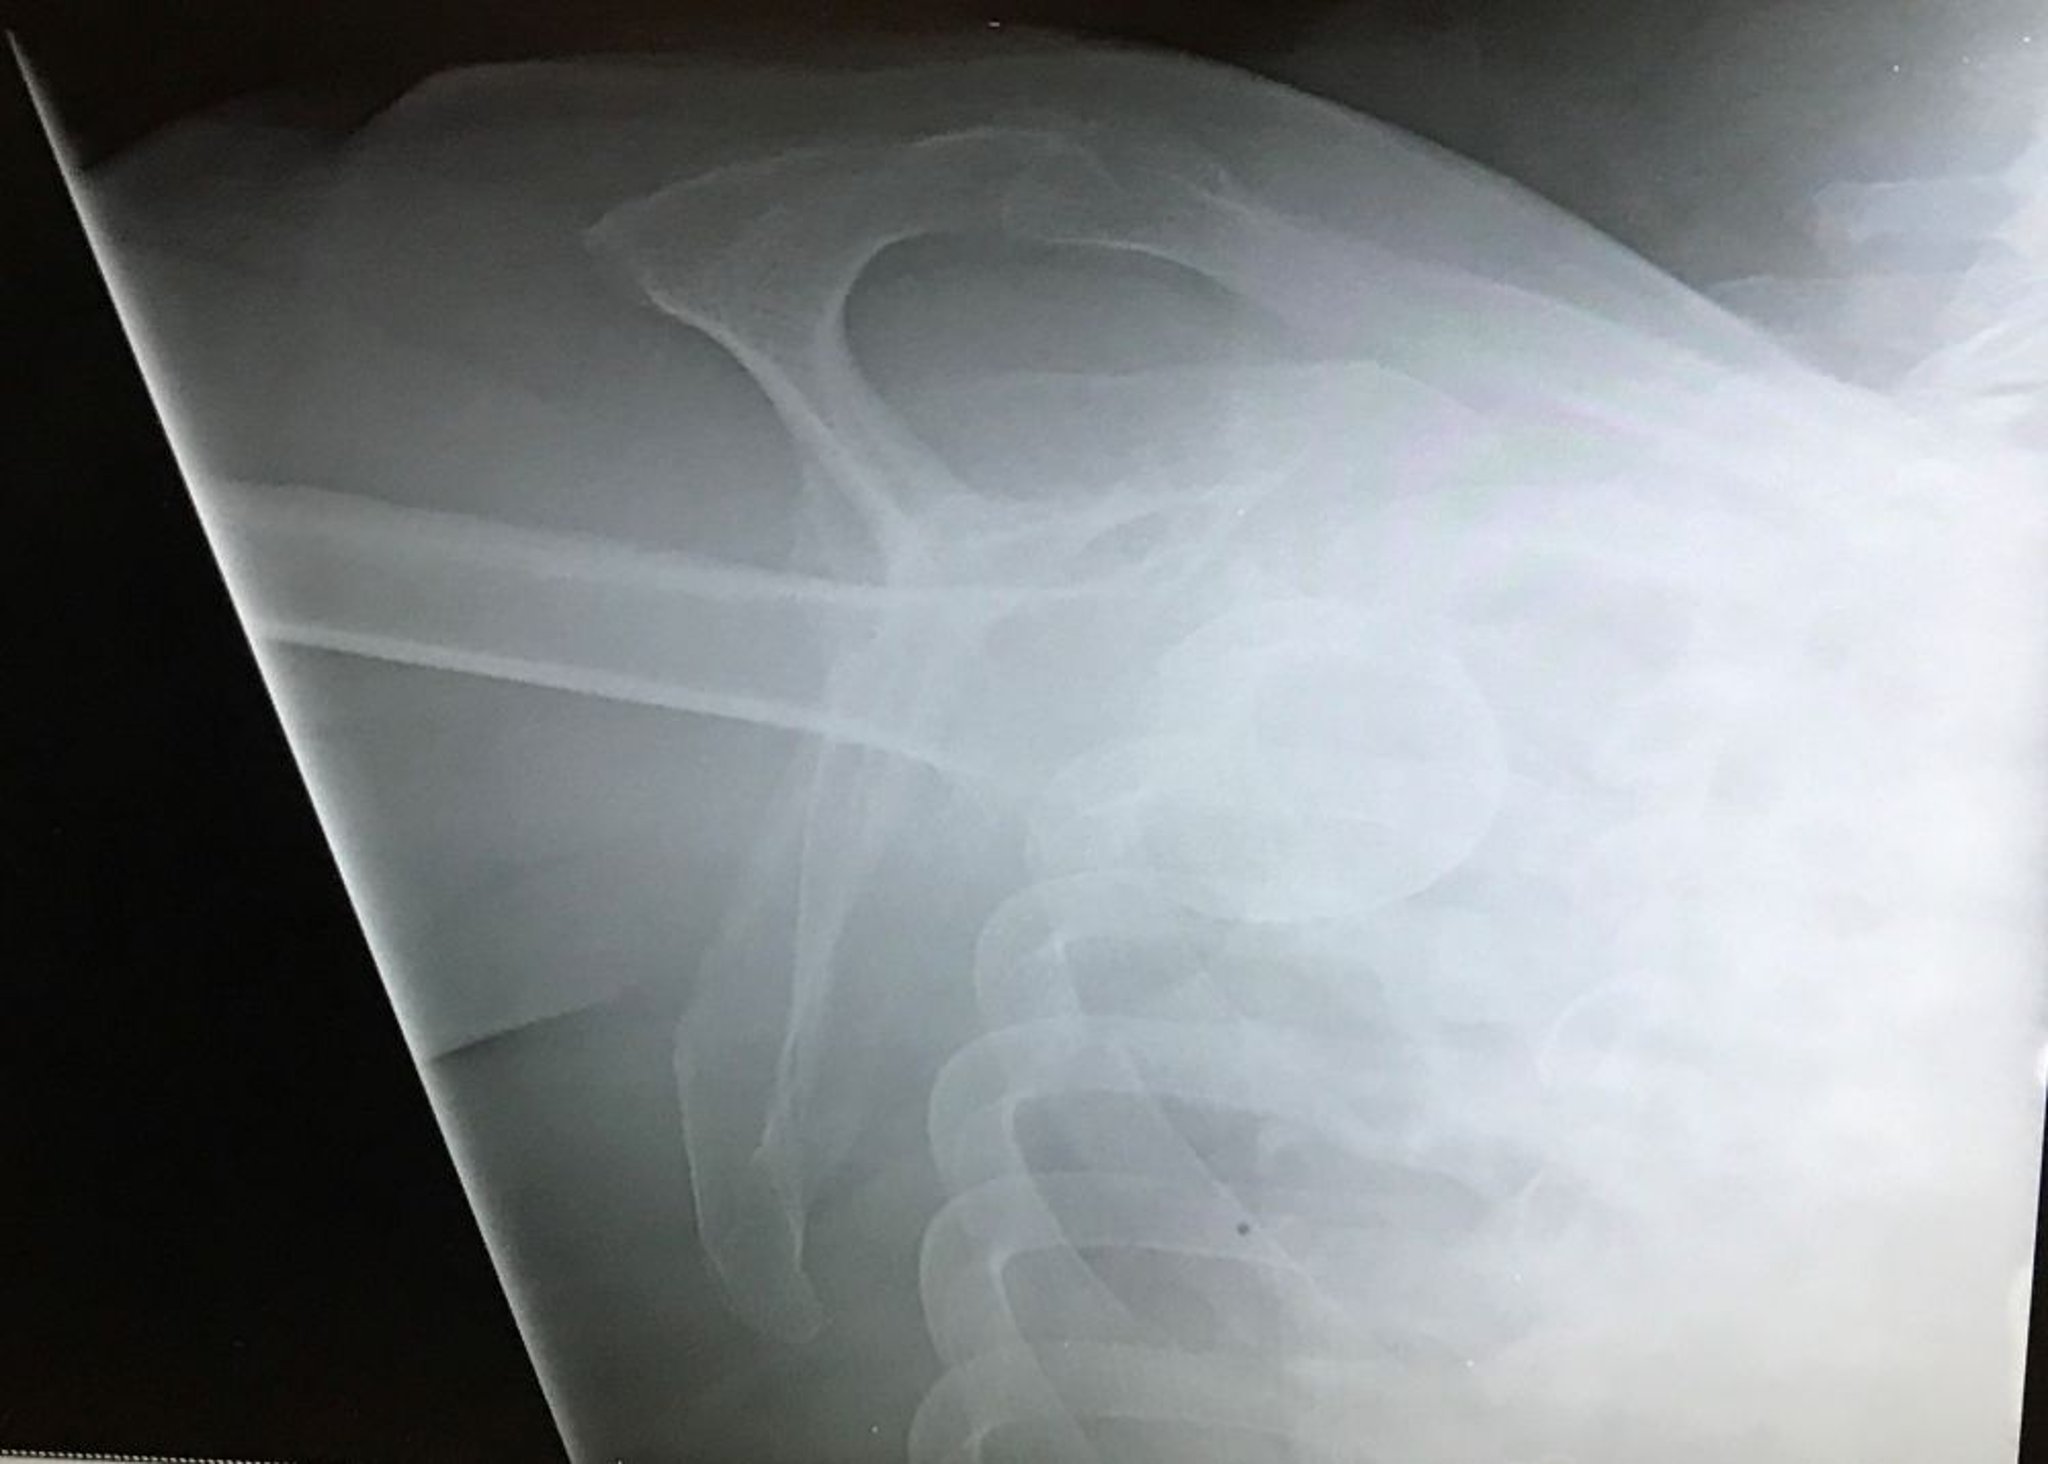

Luxación inferior del hombro

Esta vista en Y del hombro muestra la cabeza del húmero por debajo de la fosa glenoidea conel miembro en dirección cefálica, lo que indica una luxación glenohumeral inferior (luxación erecta).

Image courtesy of Danielle Campagne, MD.